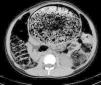

Realizamos tacto rectal, donde se palpa fecaloma de consistencia pétrea y analítica de sangre descartándose hipotiroidismo, celiaquía, etc. Posteriormente, se realizan enema opaco, ecografía y tomografía computarizada abdominal que muestra megarecto-megasigma con gran fecaloma (fig. 3).